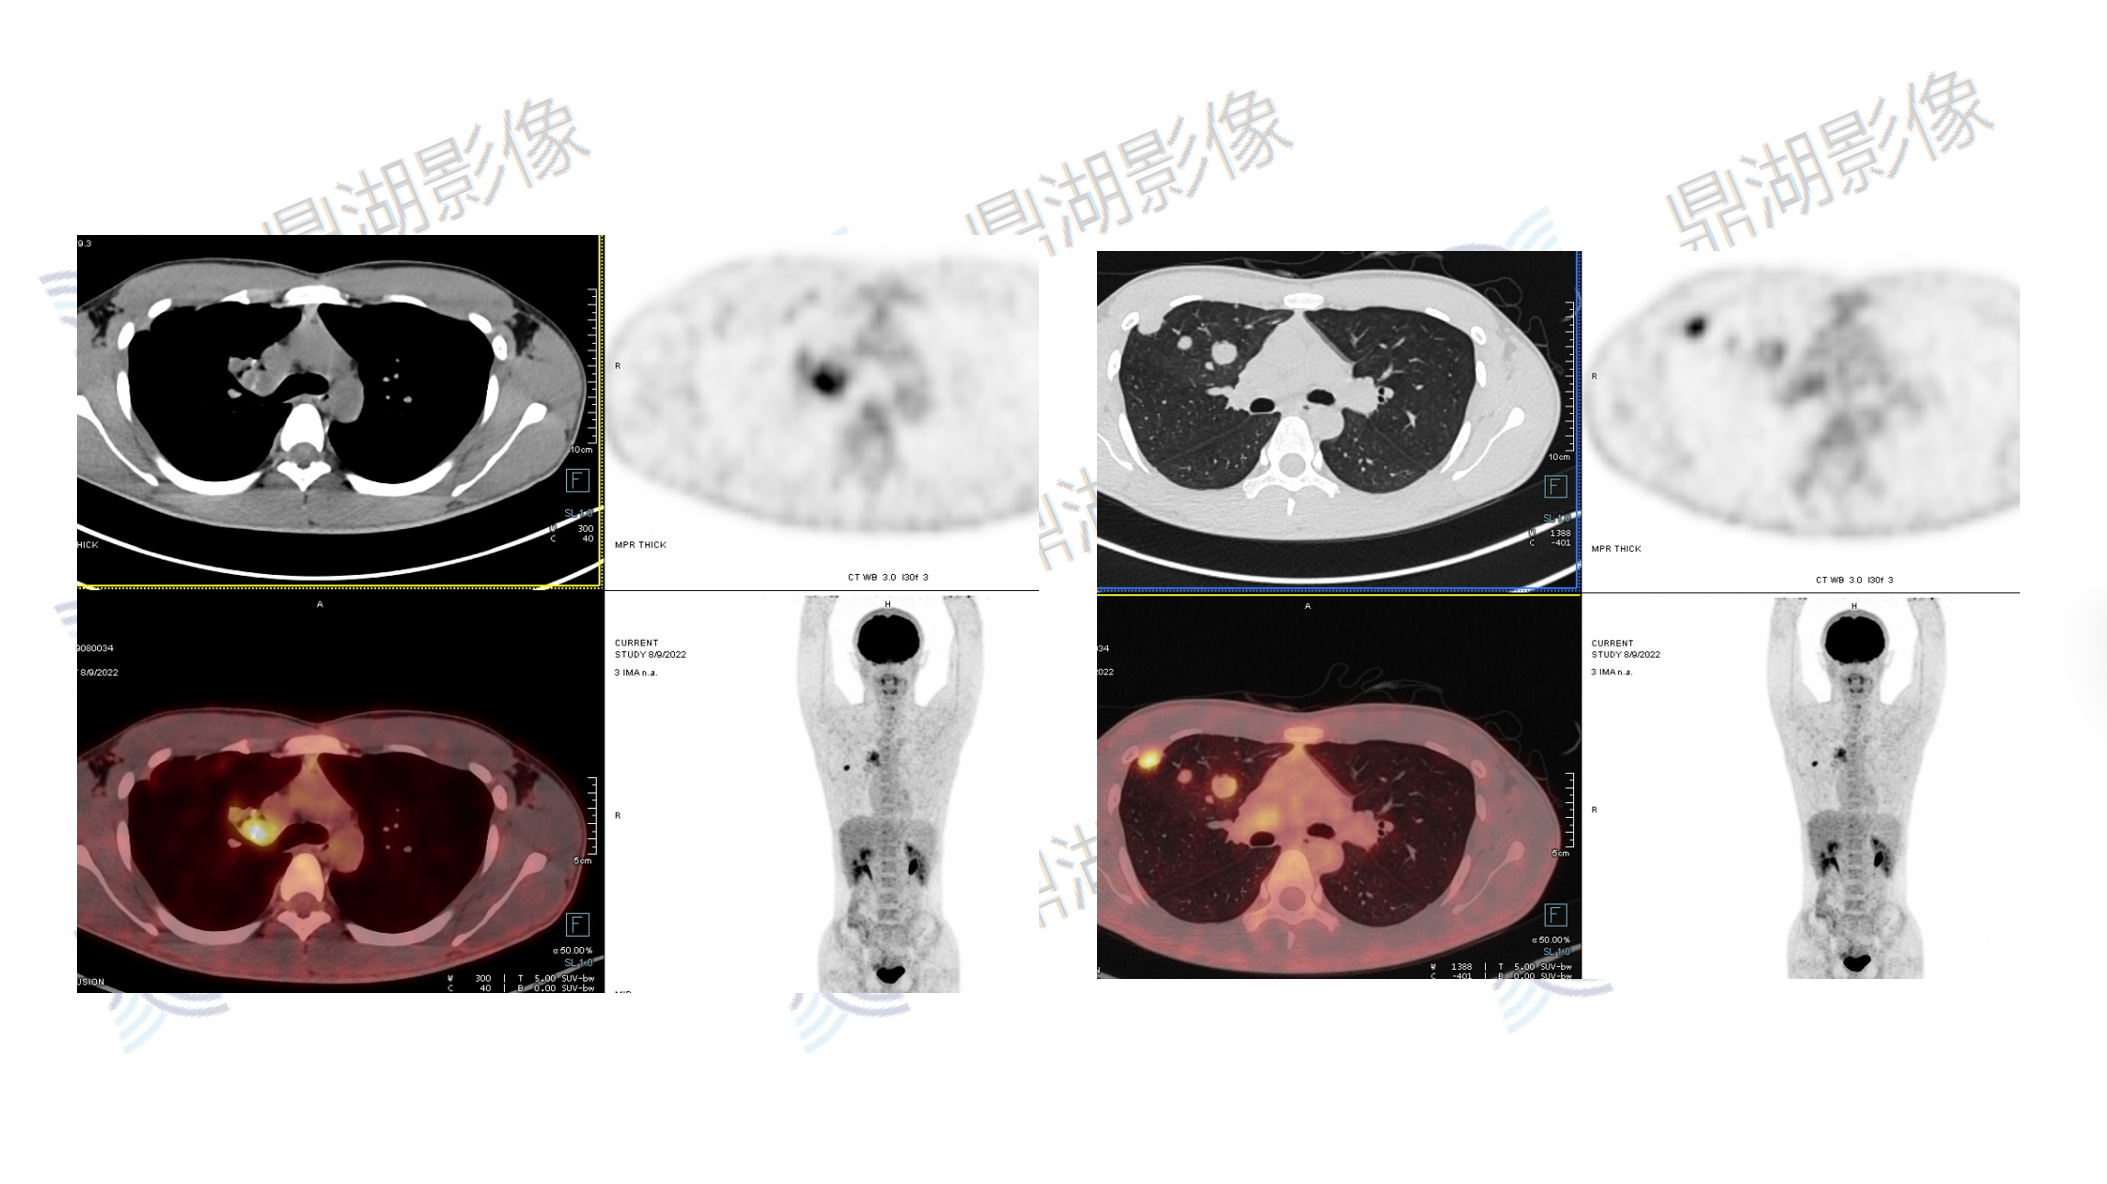

肺动脉内膜肉瘤

性别:男

年龄:20

主诉:咳嗽3月